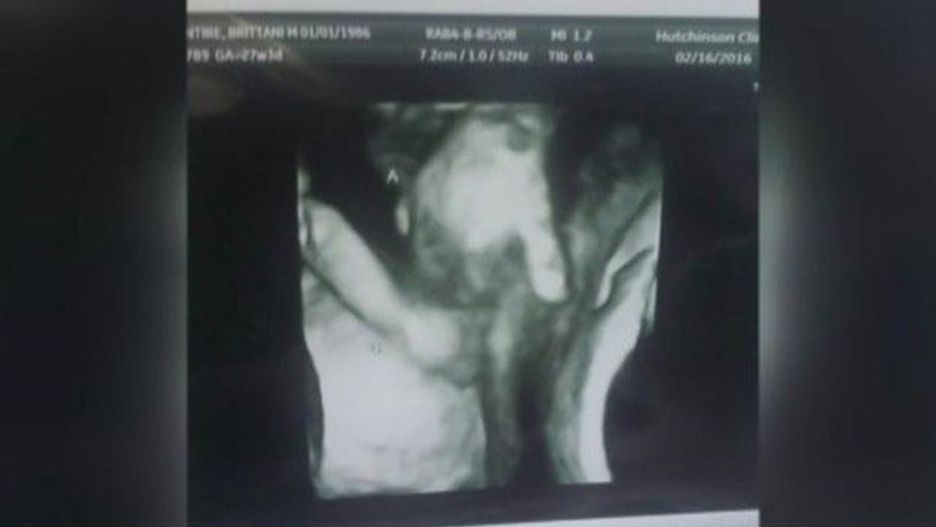

W ostatnich dniach w internecie pojawił się wzruszający obrazek: sonogram ukazujący moment, kiedy umierający brat bliźniak trzyma w łonie matki rękę siostry. Przyszli rodzice, Ian i Brittani McIntire, byli załamani, kiedy dowiedzieli się, że jedno z bliźniąt nie przeżyje.

Lekarze zajmujący się parą z Kansas stwierdzili na podstawie badań prenatalnych, że nienarodzony syn Mason ma wadę serca oraz mózgu. Jednak rodzina wciąż wzrusza się na widok zdjęcia zrobionego za pomocą sonogramu, na którym uchwycono, jak bliźnięta trzymają się za ręce. Na ujęciu widać, jak syn Mason, po lewej, trzyma małą dłonią palec siostry, Madilyn.

Rodzice bliźniąt uważają, że ta wyjątkowa chwila pomiędzy rodzeństwem to nie przypadek. Dzięki temu zdjęciu wiedzą, że będą mieli ich cząstkę razem, na zawsze. Matkę bliźniąt pociesza myśl, że jeśli malec nie przeżyje, nie będzie sam.

Lekarze poinformowali parę, że jedyną szansą na przeżycie syna jest przeprowadzenie operacji serca, jednak nie mogą ryzykować, ponieważ u rozwijającego się dziecka występują również wady mózgu. Lekarze nie są w stanie pomóc Masonowi, dlatego rodzice muszą z niepokojem czekać na rozwój wypadków i na to, czy w końcu będą mieli szansę poznać syna.

Bliźnięta mają urodzić się we wrześniu. Jednak lekarze ostrzegają rodziców, że ich syn, niestety, może umrzeć jeszcze w łonie matki przed spodziewaną datą porodu.